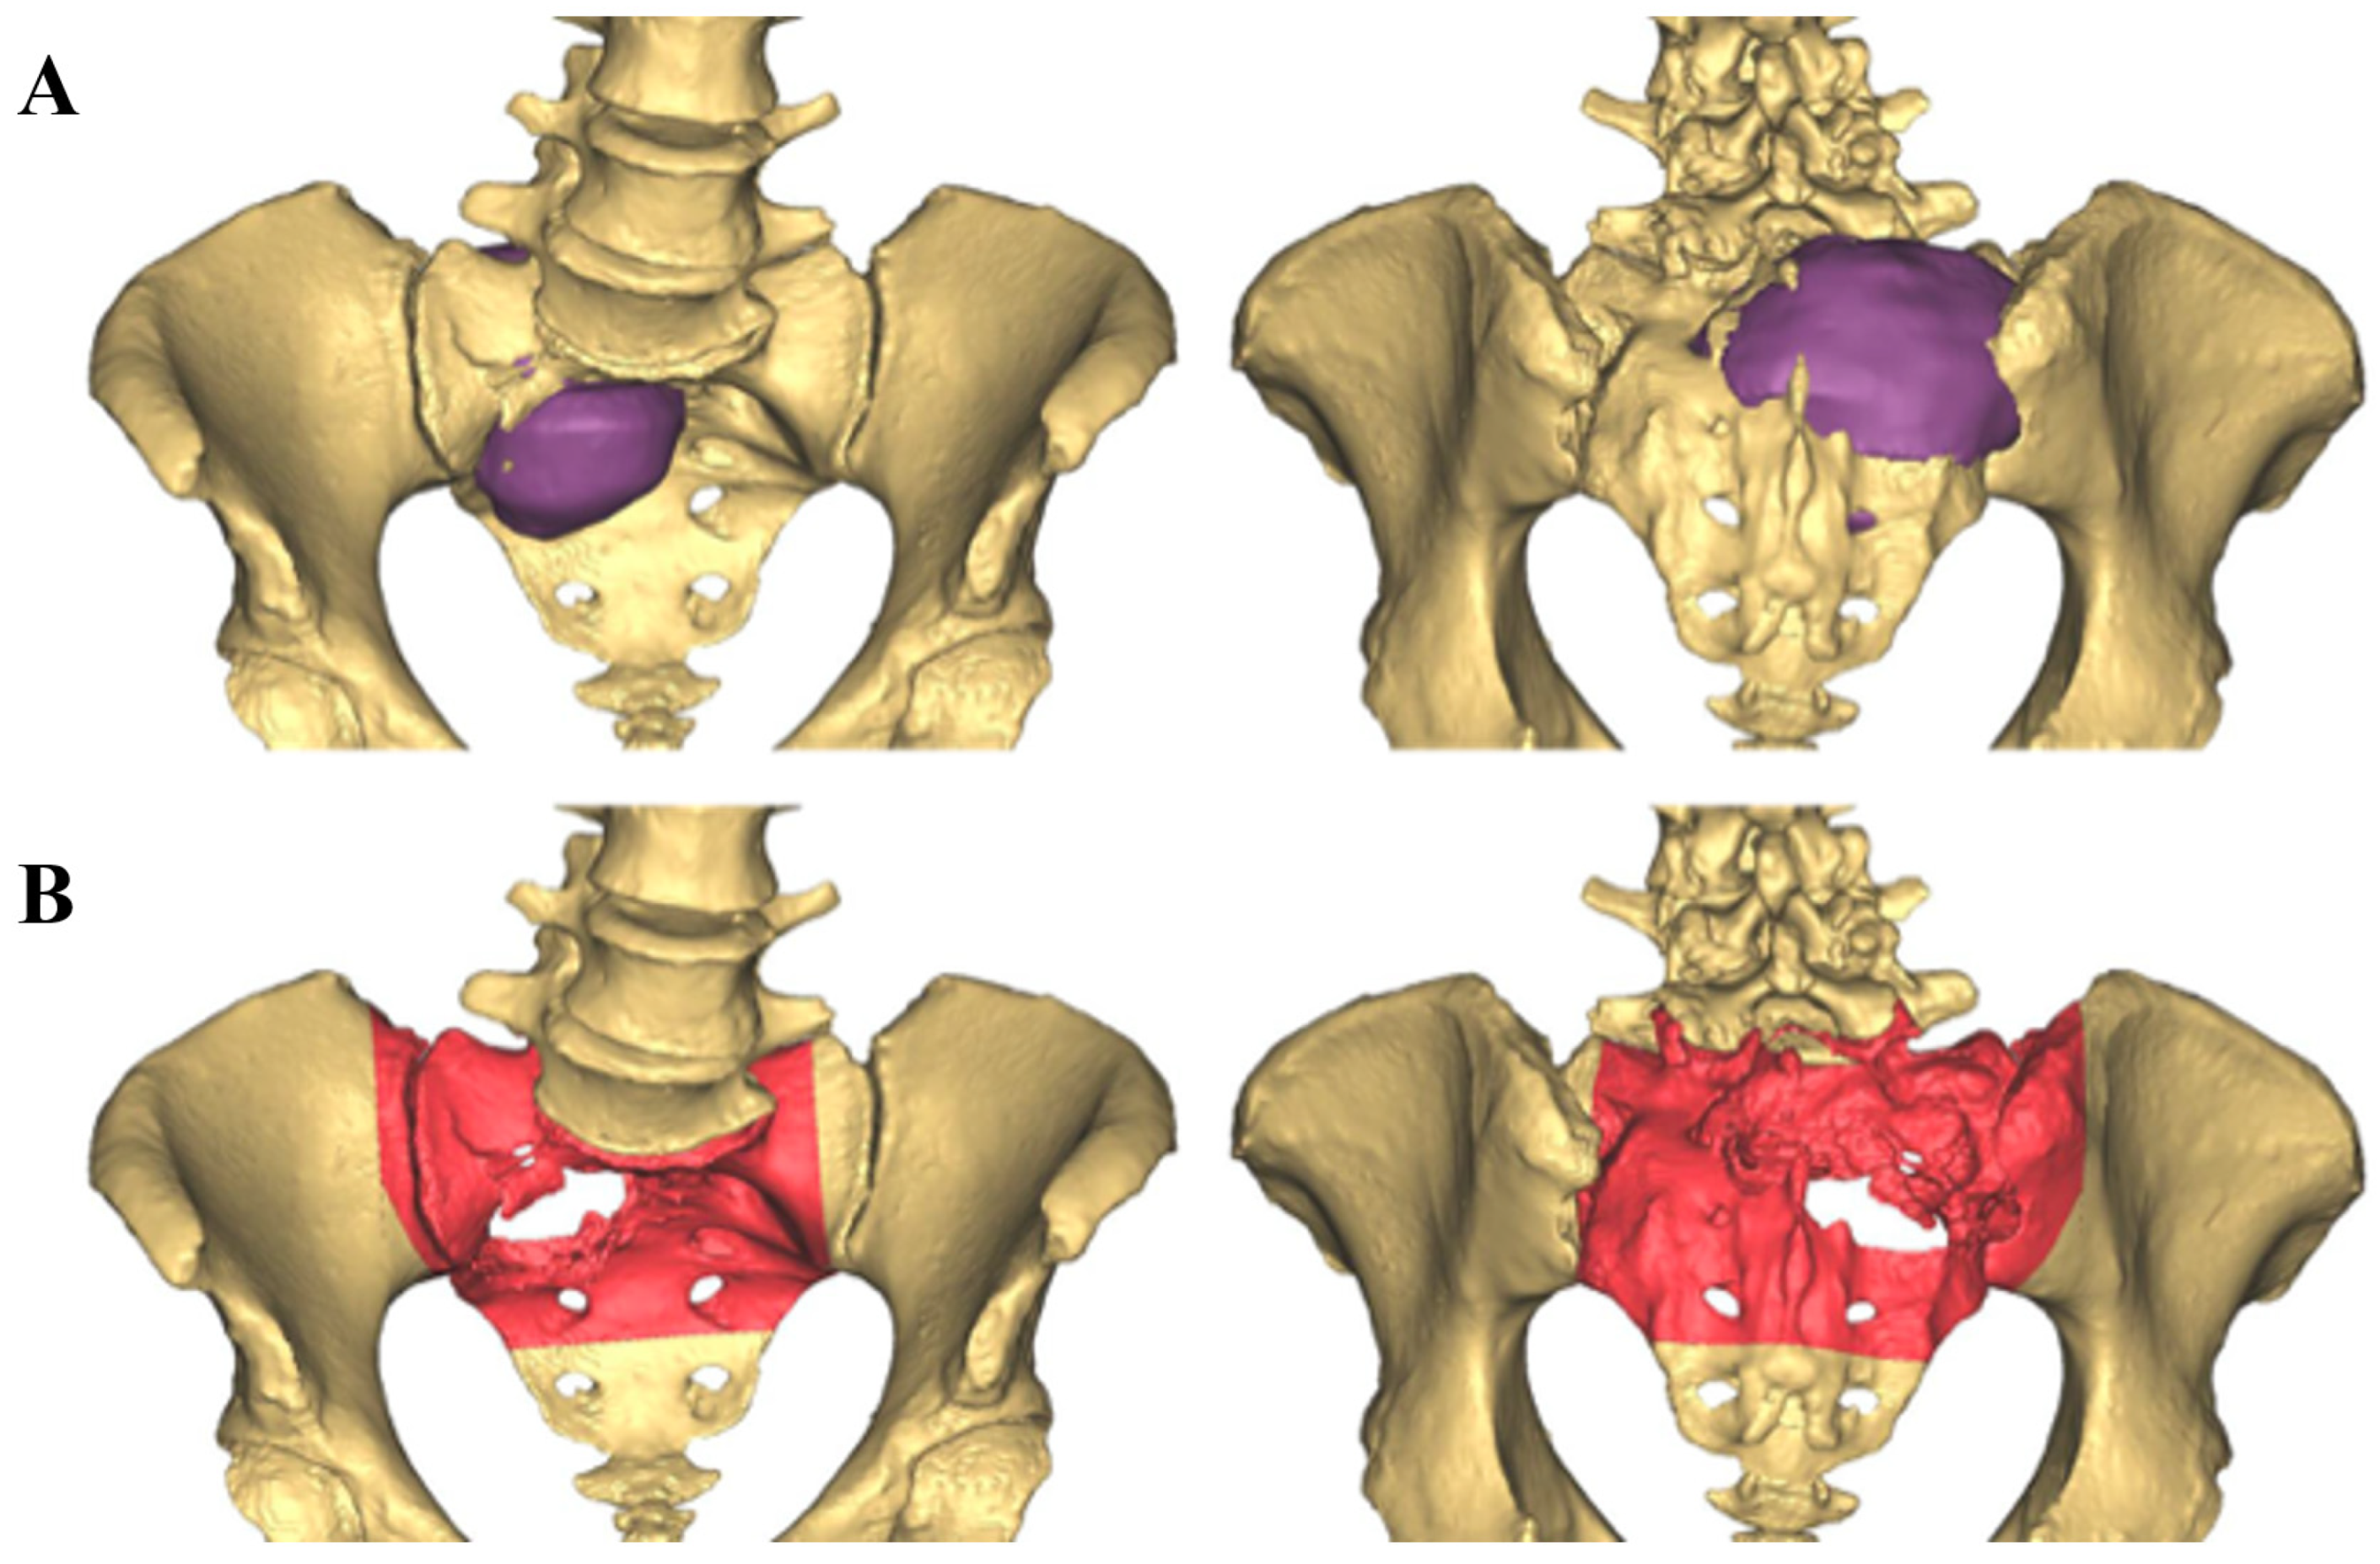

2.1. CAD Development

| Diagnosis | Radiation-Induced Osteosarcoma | Primary Osteosarcoma | Primary Chondrosarcoma | MHE, Secondary Chondrosarcoma | Primary Chondrosarcoma | Primary Chondrosarcoma |

| Location | Sacrum, Rt ilium | LS spine, Lt ilium | Lt acetabulum | Lt ilium | Sacrum, Lt ilium | Sacrum, Lt ilium |